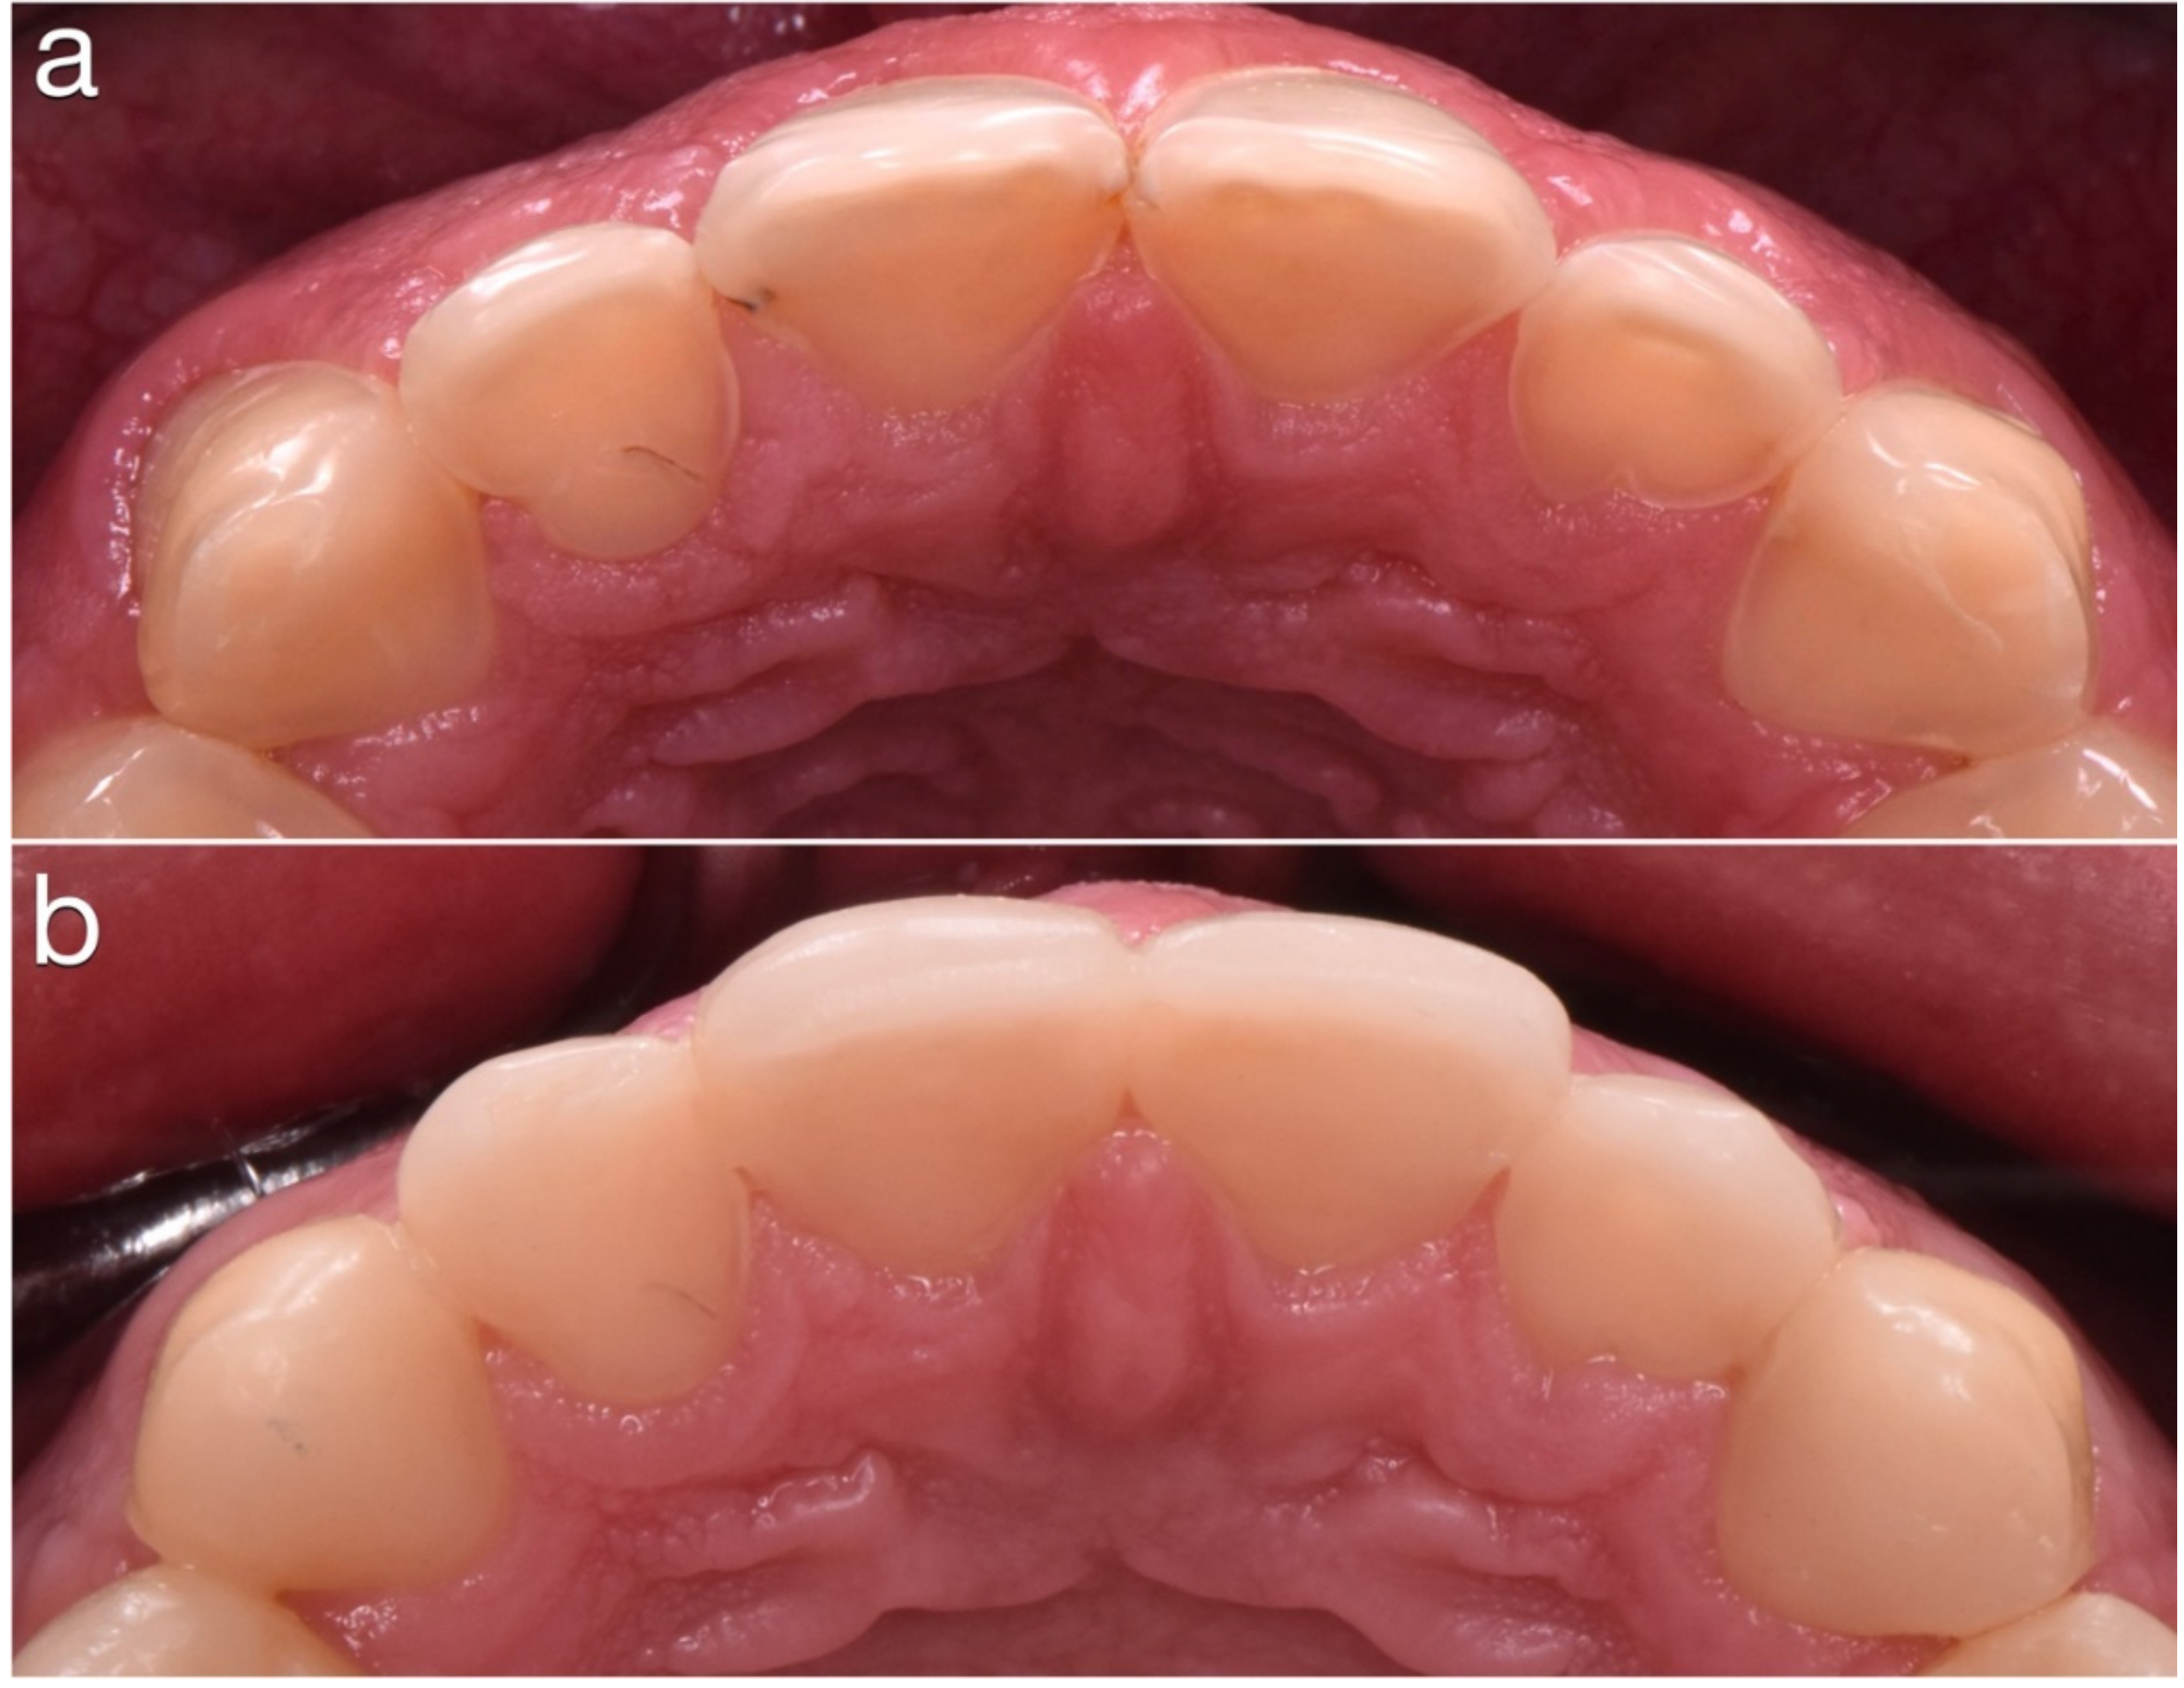

2. Clinical Report

2.1. Planning Phase

2.2. Restorative Phase